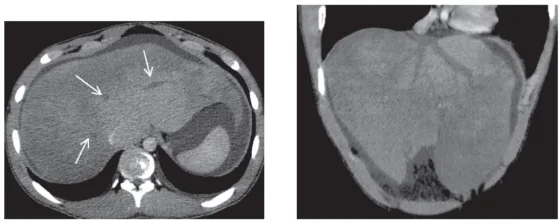

Bloc sus-hépatique

Que ce soit le syndrome de Budd-chiari par obstruction des veines sus hépatiques (Fig. 2) ou par insuffisance cardiaque droite, l’ascite est en général riche en protides. Le syndrome de Budd-chiari doit faire réaliser un bilan d’une thrombophilie constitutionnelle ou acquise. Une ascite liée à une insuffisance cardiaque droite peut survenir au cours d’une cardiopathie aiguë ou chronique et doit faire éliminer une péricardite constrictive ou une embolie pulmonaire massive. Les explorations radiologiques des veines sus hépatiques et cardiologiques par cathétérisme droit permettent de confirmer le diagnostic.

Il s’agit le plus souvent d’une maladie vasculaire du foie avec une hypertension portale non cirrhotique [13]. De multiples maladies vasculaires du foie sont associées à une hypertension portale non liée à la cirrhose (Tableau III). En effet chez le patient cirrhotique, le gradient porto-sus hépatique > 5 mm/Hg est lié à l’augmentation de la résistance sinusoïdale alors que dans l’hypertension portale non cirrhotique, le gradient porto sus-hépatique est le plus souvent normal ou très modérément élevé avec une pression dans la veine porte qui est normale. L’hypertension portale non cirrhotique inclut des maladies vasculaires diverses dont la classification dépend du siège de l’augmentation des résistances vasculaires qui peut être sinusoïdale, pré-sinusoïdale ou plus rarement post-sinusoïdale (Tableau III). L’imagerie par scanner peut donner un élément d’orientation en précisant le caractère homogène ou nodulaire du foie (Fig. 2) et la perméabilité des veines sus hépatiques ou du tronc porte (Fig. 3).

Sur la reconstruction coronale, on ne visualise que les veines moyenne et gauche (collection Pr Otal, Radiologie CHU Rangueil Toulouse)